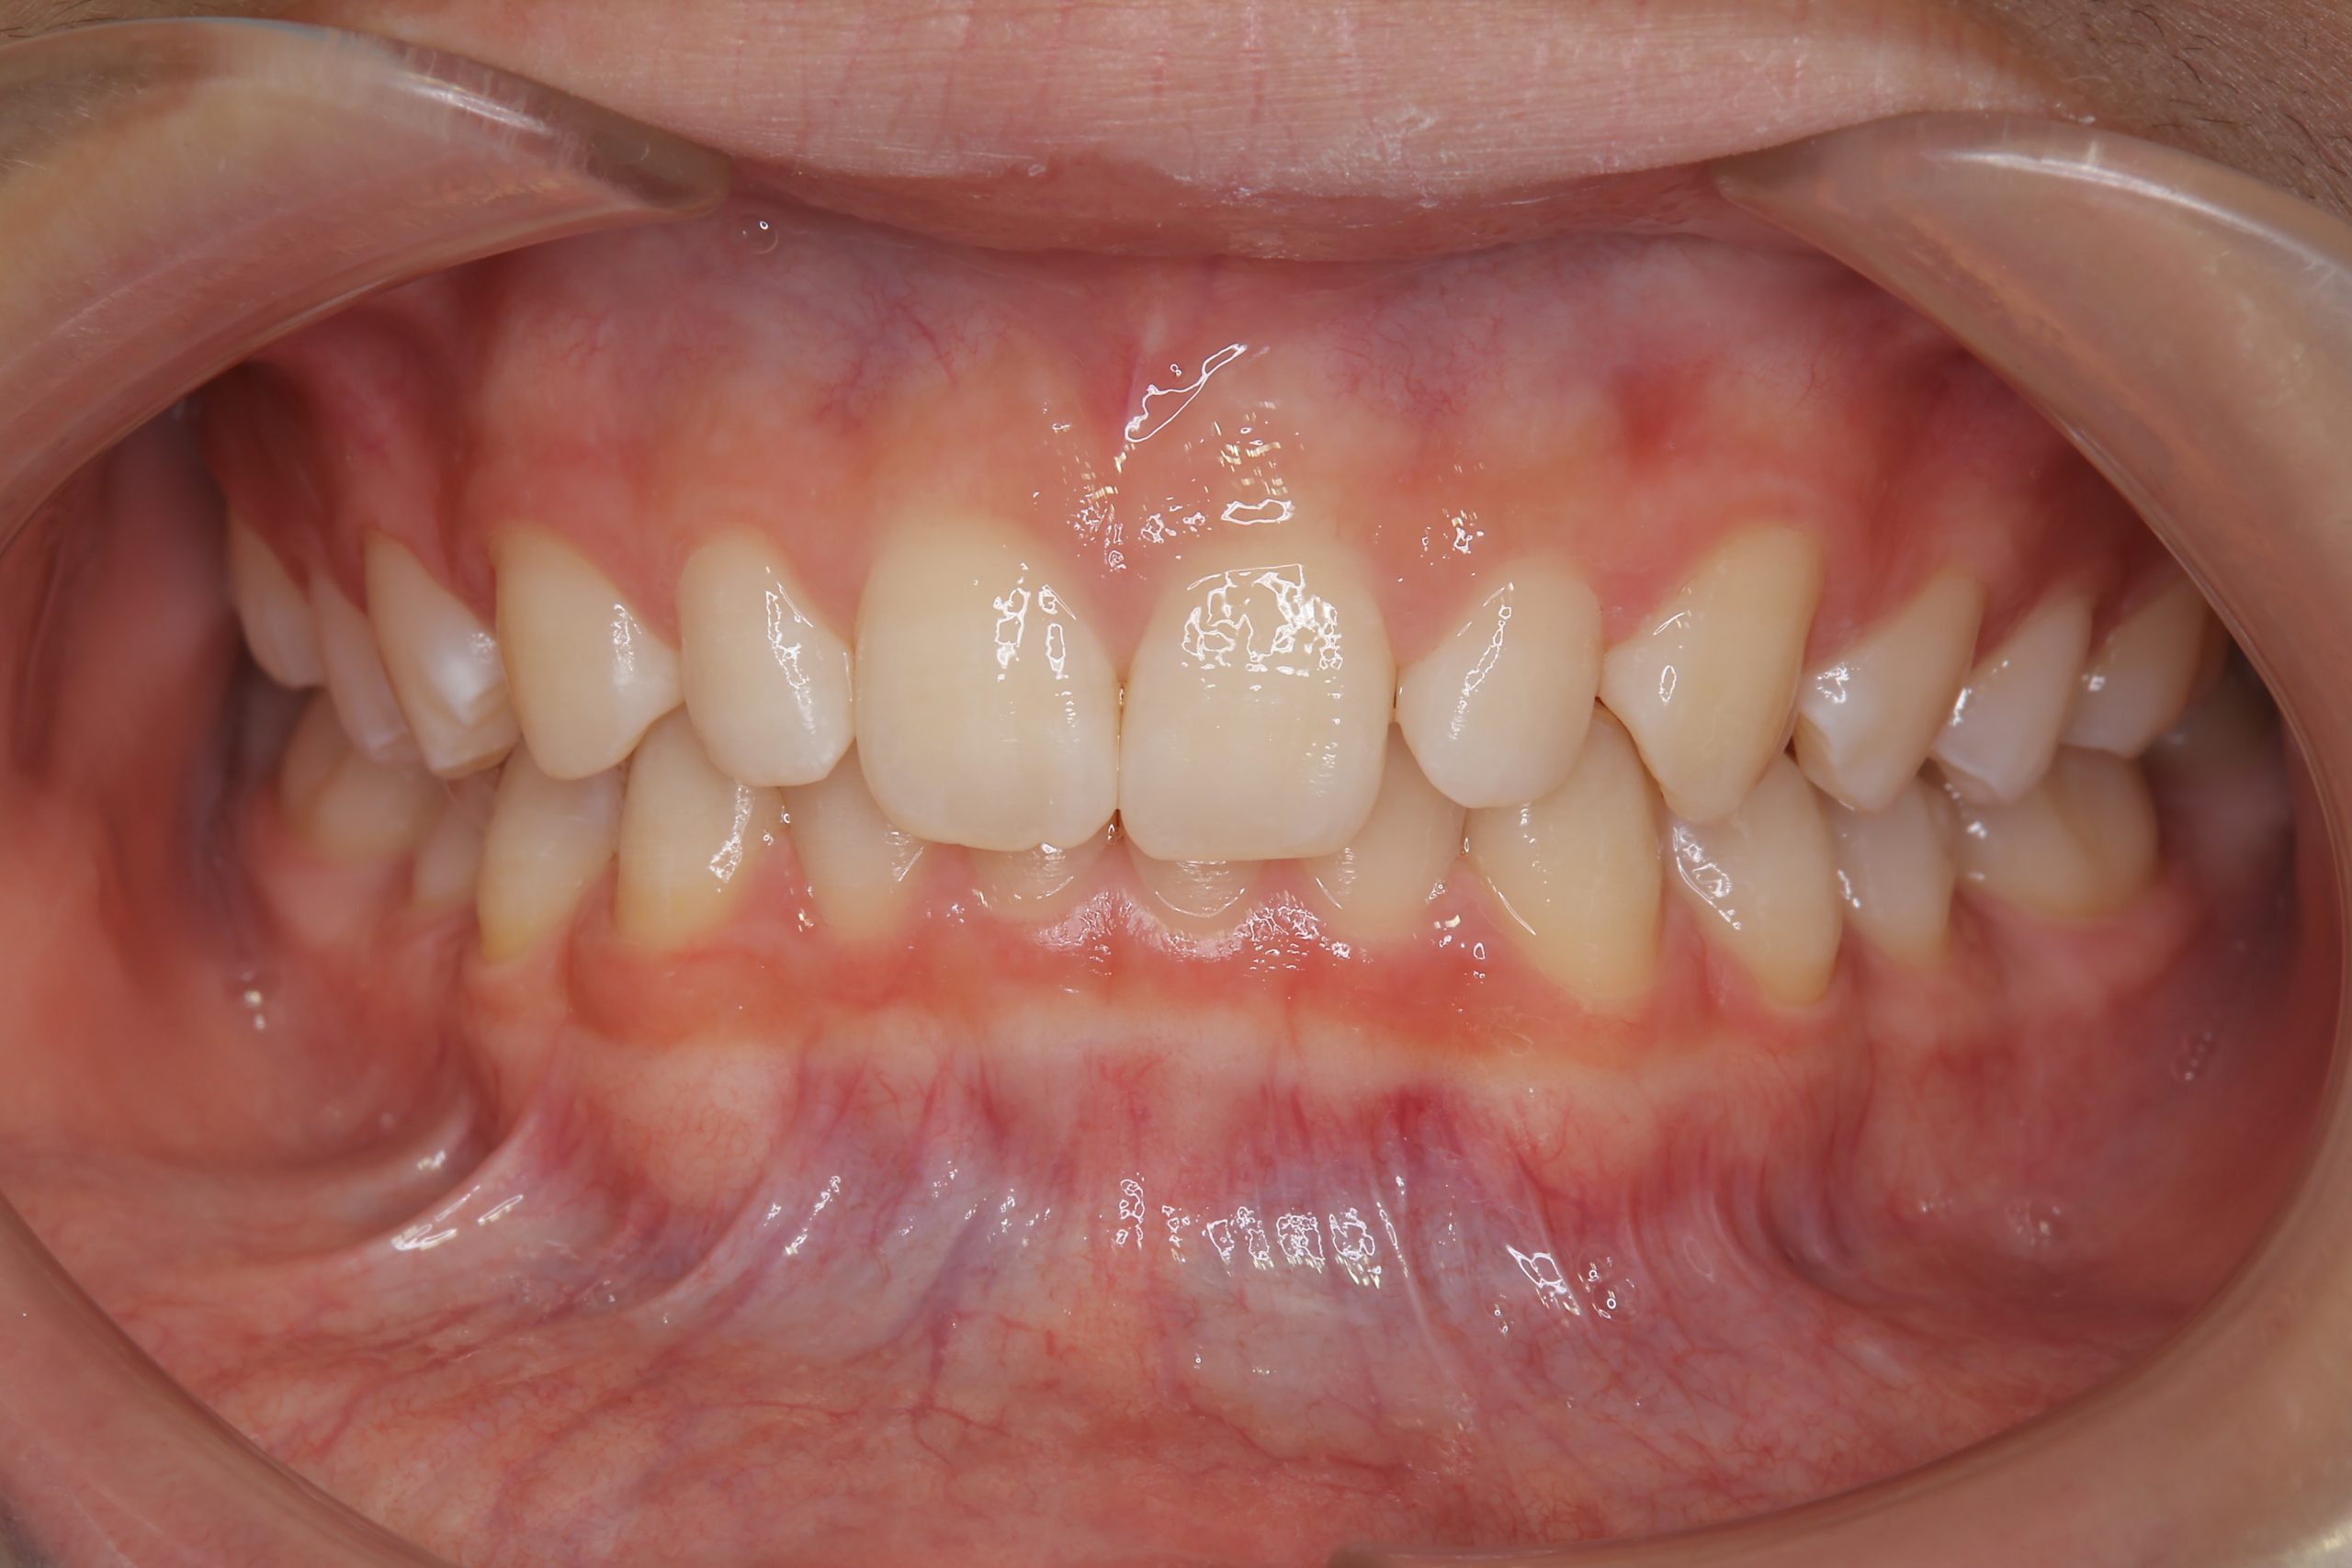

アフター

子どもの矯正治療|症例_121

主訴 歯並び

施術内容 上顎急速拡大装置と下顎リンガルアーチを用いて上下顎骨を拡大した。

その後マウスピース型矯正装置で歯牙を配列し良好な咬合を獲得した。

治癒期間 3年11ヶ月間